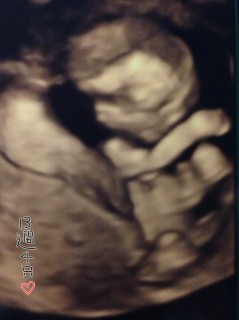

Baby 7.68cm 大きく成長してる!

元気に動いてますねと言われました。一応性別も診てもらいましたが、まだ分かりませんでした!7.07cmです♪

やっと人間らしい形になってきました!

背骨がしっかり見えて、感動しました。

顔がミッキーマウスみたいで、メッチャ可愛い(*´∀`*)

手を頭の後ろにして

腹筋をしているような

体勢をしています。

このとき性別わかりました!

男の子でした(^o^)

13W